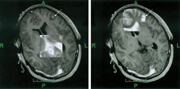

On the left, see a realtime slice (.5 Tesla) and, on the right, the

corresponding image from a preoperative volume (3D sequence, .5 Tesla). The

LOCALITE iMRI Navigator lets the surgeon use specific vizualizations to

compare the realtime image and corresponding images from the planning

phase. When deviations are detected, the surgeon may acquire a current

iMRI volume and update the plan on its basis. This may be repeated as

necessary, leading to a process of iterative navigation. For the surgeon these

options are not mutually exclusive but complementary:

The right picture above connects to the planning results, while the

realtime slice on the left lets him evaluate the residual 'goodness' of

the planning data that are no longer up-to-date.